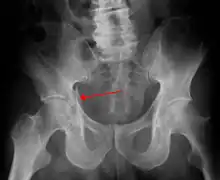

En fonction des forces appliquées sur le bassin, trois mécanismes sont décrits :

- La compression antéro-postérieure : elle endommage d'abord les ligaments de la symphyse pubienne, suivi de la rupture des ligaments du plancher pelvien (ligaments sacro-iliaques), et enfin fracture des deux cadres obturateurs.

Dans le cas de fracture du bassin par compression antéro-postérieure, dite open book « à livre ouvert », la symphyse pubienne peut se rompre et s'écarter en s'ouvrant comme un livre. La cavite du bassin augmente de volume, et ne joue plus son « rôle tampon » en restant fermée. Le risque principal est alors l'hématome du rétropéritoine qui peut aller jusqu'à 4 litres de sang, avec déséquilibre hémodynamique et état de choc hypovolémique[4],[11].